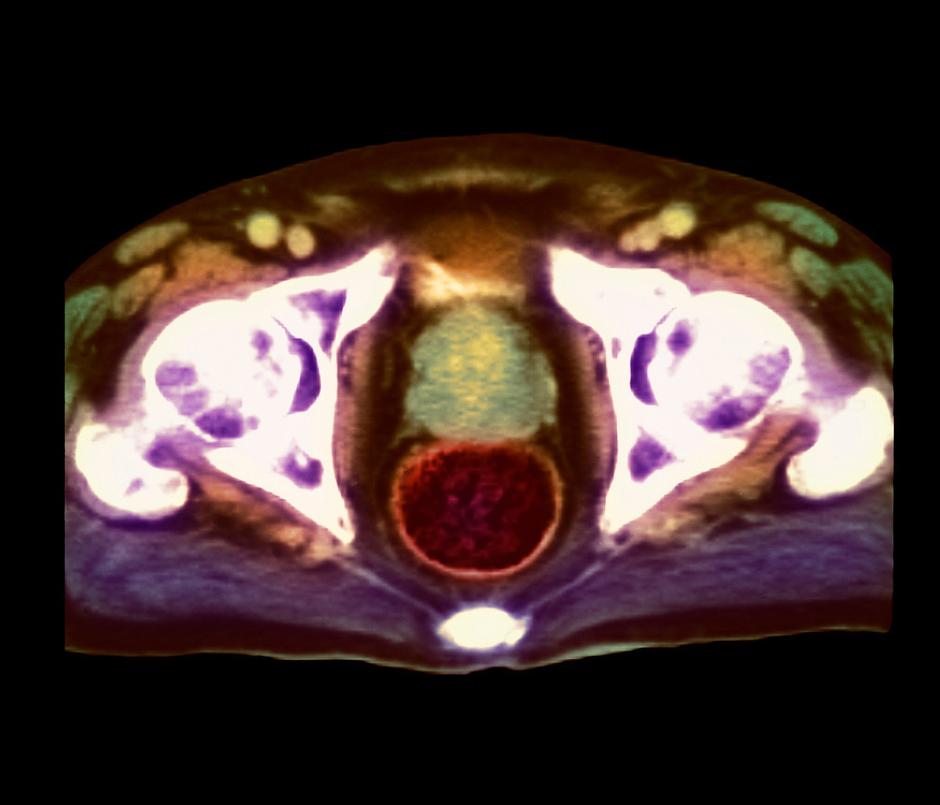

Rak prostate | Avtor: Profimedia Profimedia

Rak je genetska bolezen in je posledica sprememb v genih, ki nadzorujejo delovanje naših celic. "Rak je  posledica mutacije na našem genomu.Te mutacije se sicer dogajajo od našega rojstva ves čas, na srečo imamo neke mehanizme, ki te mutacije lovijo in jih popravljajo. Vendar, če enkrat ena sama celica pobegne tem popravljalnim mehanizmom in se začne deliti, nastane skupek, klon večih celic in takrat govorimo, da se začne rak. Na začetku še ni simptomov, ko pa se te celice delijo in množijo, rak raste in takrat se pojavijo simptomi in takrat raka tudi običajno odkrijemo," nastanek te težke bolezni opiše Irena Oblak, dr. med., strokovna direktorica Onkološkega inštituta Ljubljana: